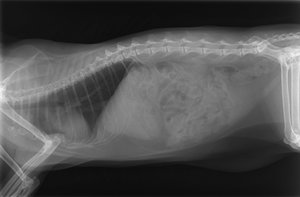

Diskutiere Habe GROßE ANGST um meinen JEREMY!!! im Besuch beim Tierarzt Forum im Bereich Katzenkrankheiten; Hier die RÖ BILDER

Hier die RÖ BILDER

Auch wenn ich kein Tierarzt bin, aber die Röntgenbilder sehen gut aus.

Hat Tierarzt auf Rheuma,Gicht und vor Allem auf Athrose an den Gelenken geschaut? Ich sehe nur Wirbelsäulenbilder?

Wir haben nochmal geröntgt und da war was

Komisches wie der DOC sagt, im/am Darm!

Das KOMISCHE auf dem Röntgenbild, war KOT und kein Tumor!!